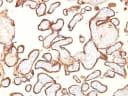

Reacts with a 70 kDa membrane-bound isozyme (Regan and Nagao type) of Placental Alkaline Phosphatase (PLAP) occurring in the placenta during the 3rd trimester of gestation. It is highly specific for PLAP and shows no cross-reaction with other isozymes of alkaline phosphatase. Anti-PLAP reacts with germ cell tumors and can discriminate between these and other neoplasms. Somatic neoplasms e.g. breast, gastrointestinal, prostatic, and urinary cancers may also immunoreact with antibodies to PLAP. Anti-PLAP positivity in conjunction with anti-keratin negativity favors seminoma over carcinoma. Germ cell tumors are usually anti-keratin positive, but they regularly fail to stain with anti-EMA, whereas most carcinomas stain with anti-EMA. Anti-PLAP has been useful in the diagnosis of gestational trophoblastic disease._x000D__x000D_Primary antibodies are available purified, or with a selection of fluorescent CF® Dyes and other labels. CF® Dyes offer exceptional brightness and photostability. Note: Conjugates of blue fluorescent dyes like CF®405S and CF®405M are not recommended for detecting low abundance targets, because blue dyes have lower fluorescence and can give higher non-specific background than other dye colors.Synonyms:

HepG2 cells. Placenta or seminomaConcentration: